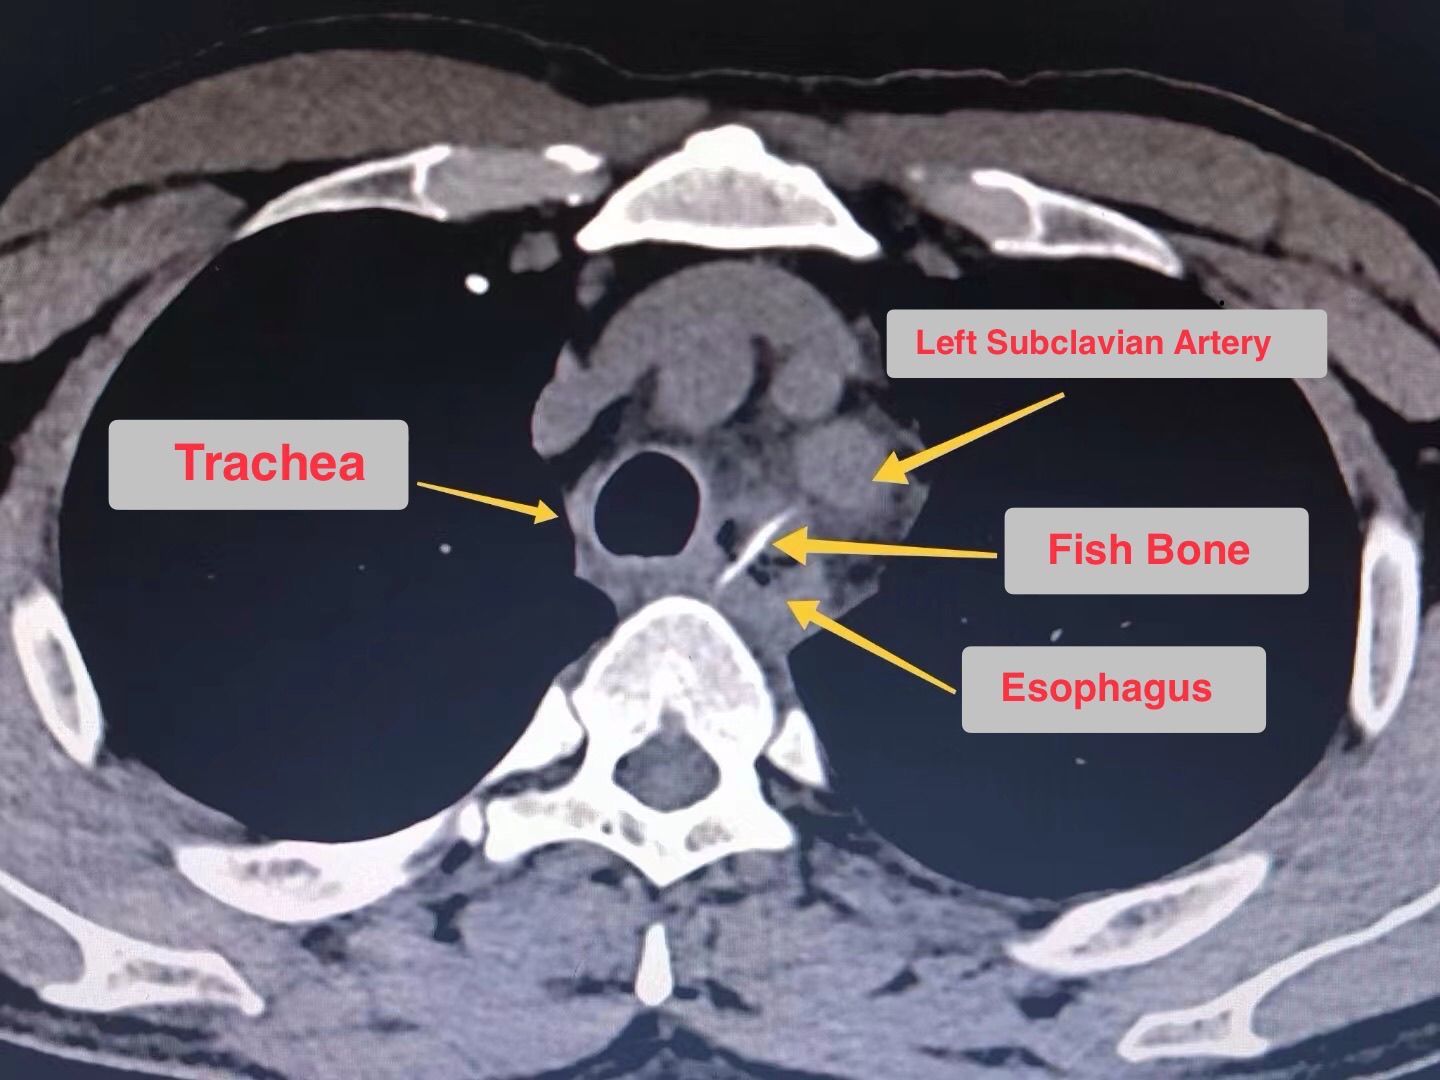

Foreign body on CT scan

Patient presented to the emergency department with complaints of foreign body in esophagus. Upon radiological investigations and clinical history of the patient, fish bone was identified in the esophagus and was surgically removed.